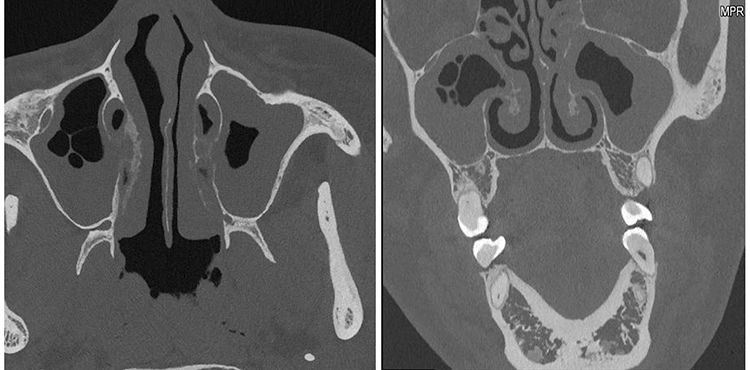

Das neue CT-Gerät von SIEMENS NAEOTOM Alpha* basiert auf dieser Technologie (Abb. 2). PCDs erlauben eine deutlich höhere Ortsauflösung, weisen kein elektronisches Rauschen auf und liefern systeminhärent Spektralinformationen über das eintreffende Röntgensprektrum [6]. Aufgrund dieser und noch weiterer technischer Eigenschaften lassen PCD-basierte Systeme eine mit heutigen Detektoren nicht denkbare Dosisreduktion erwarten [6]. Leider gibt es derzeit und wohl aus Kostengründen auch in naher Zukunft noch kein DVT mit einem PCD. Langfristig ist jedoch zu erwarten, dass diese Detektoren aufgrund ihrer vielen Vorteile sicherlich auch in der Zahnmedizin die heutigen energieintegrierenden Detektoren ersetzen werden.